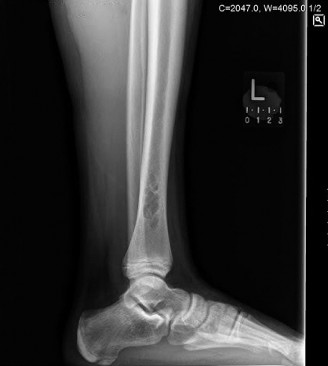

The diagnostic workup for a suspected pathological fracture secondary to multiple myeloma must be comprehensive yet expedited. Following the initial plain radiographs and the CT scan of the chest, abdomen, and pelvis, specific attention must be directed toward oncologic staging and assessing the global skeletal burden.

Therefore, relying on a standard bone scan to stage skeletal involvement in myeloma is a fundamental clinical error. Instead, the gold standard imaging modalities for staging multiple myeloma bone disease include Whole Body Low Dose CT, Whole Body MRI, or 18F-FDG PET-CT. These modalities directly visualize marrow infiltration and lytic destruction regardless of osteoblastic response, providing an accurate map of impending structural failures throughout the axial and appendicular skeleton.